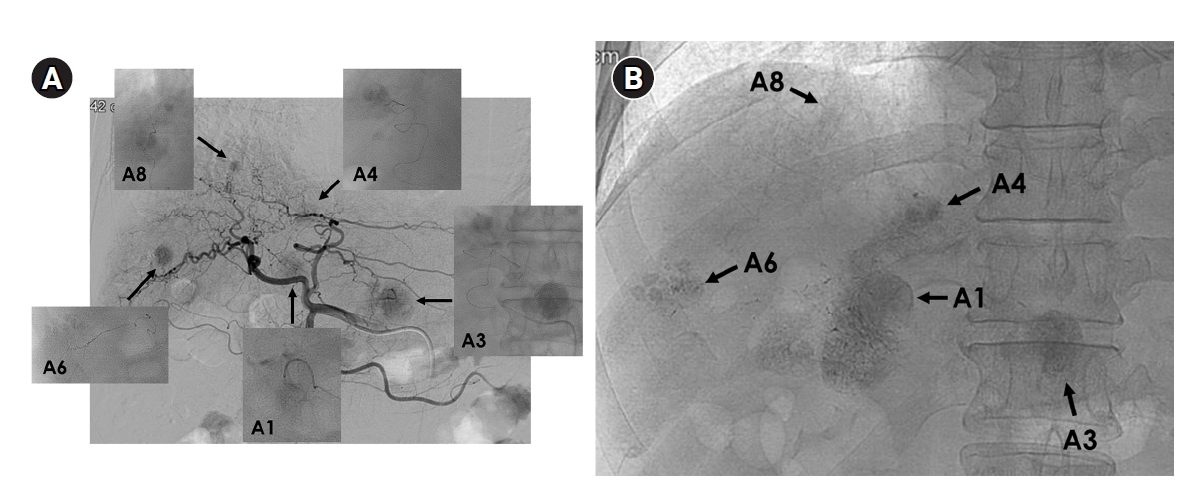

Fig. 3.

Central bile duct injury after transarterial radioembolization in an 80-year-old woman with ruptured hepatocellular carcinoma. (A) Computed tomography obtained 5 months after selective infusion of Y-90 microspheres via A1, A4, and A8 shows extensive radiation necrosis (arrows) in segments 4 and 8, with dilatation of the intrahepatic bile ducts (circle) in the left lateral segments. (B) Because of progressive jaundice and pruritus, percutaneous transhepatic biliary drainage was performed, and cholangiography showed segmental occlusion of the left main bile duct (arrow), suggesting radiation-induced ductal injury.

Fig. 3. Central bile duct injury after transarterial radioembolization in an 80-year-old woman with ruptured hepatocellular carcinoma. (A) Computed tomography obtained 5 months after selective infusion of Y-90 microspheres via A1, A4, and A8 shows extensive radiation necrosis (arrows) in segments 4 and 8, with dilatation of the intrahepatic bile ducts (circle) in the left lateral segments. (B) Because of progressive jaundice and pruritus, percutaneous transhepatic biliary drainage was performed, and cholangiography showed segmental occlusion of the left main bile duct (arrow), suggesting radiation-induced ductal injury.